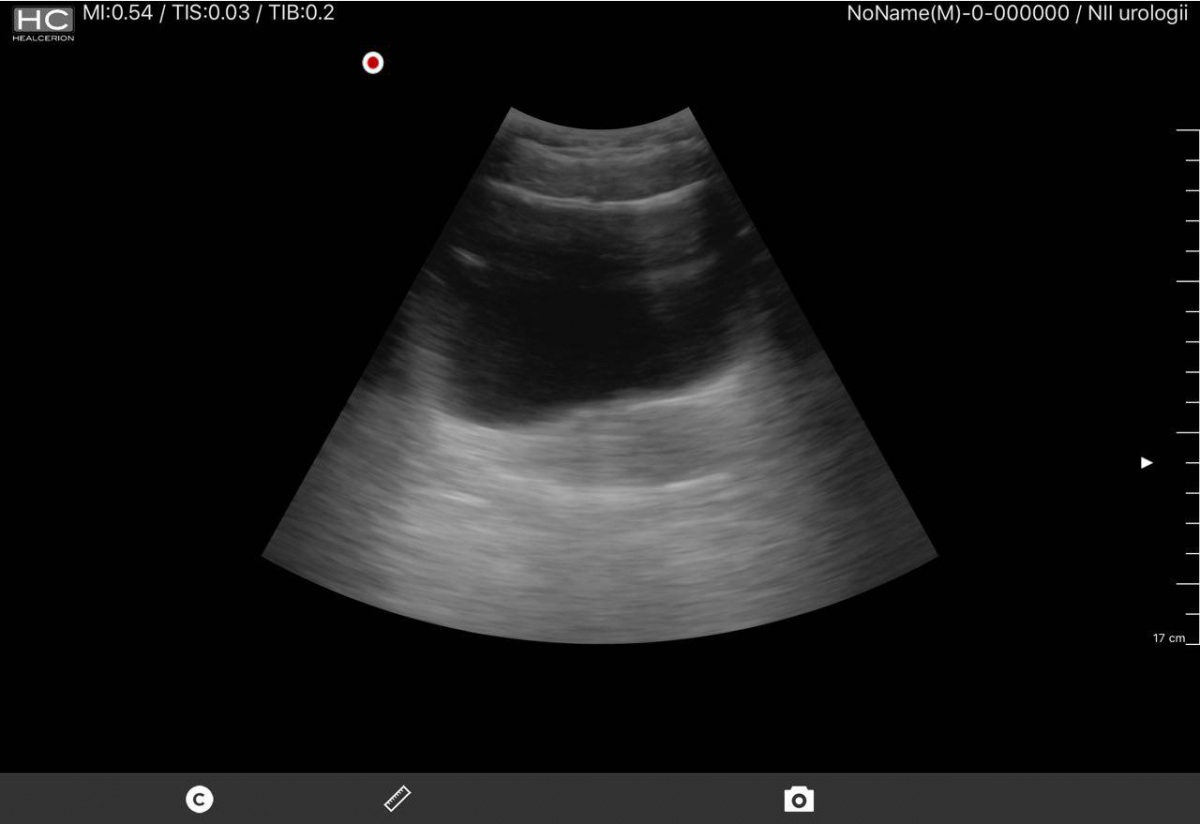

Ниже небольшая галерея скриншотов (почка, мочевой пузырь)

Качество изображения удовлетворительное, оно конечно же несколько не дотягивает субъективно до стационарных аппаратов экспертного класса, но посоревноваться с прочими переносными аппаратами еще как может. Датчик при всей его портативности все же не легкий, уже появляются аналоги чуть ли не в два раза легче. Очень раздражает постоянный шум вентилятора.